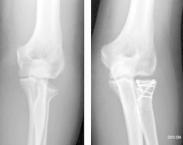

橈骨頭的頭、頸部骨折約占肘部損傷的6%,屬于關(guān)節(jié)內(nèi)骨折。由于橈骨頭、頸骨折的固定需要特殊的技術(shù)和方法才能達(dá)到穩(wěn)定,這在臨床上不易做到,因此,目前橈骨頭、頸骨折的治療和處理方法仍存在很多爭議。